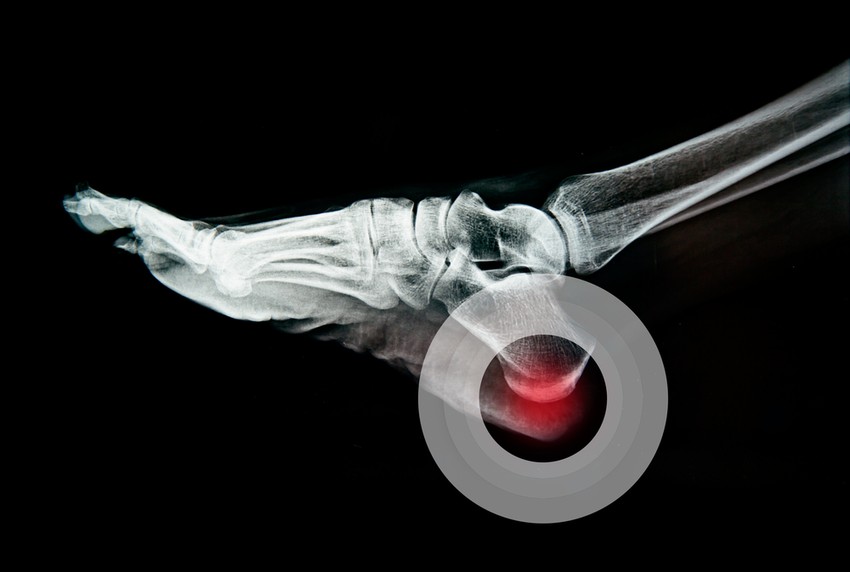

A láb sarokcsontja a lendületből adódóan minden egyes lépésnél – a futásról nem is beszélve – a test súlyánál nagyobb terhelésnek van kitéve. A sarokcsont és a lábujjak között feszülő kötőszövet (talpi bőnye) úgyszintén minden egyes lépésnél dolgozik: megfeszül, majd elernyed. Ha ez a folyamat túl megerőltető módon, ideig vagy valamiféle pluszterheléssel játszódik le, bekövetkezik a nagyon gyakori és fájdalmas tünet: a sarokfájdalom.

Az ín–csonthártya találkozásánál gyulladás (talpi bőnye gyulladás) alakul ki , és ha a gyulladás hosszú ideig fennáll, csontkinövés keletkezik. A sarki csontkinövés, sarkantyúképződés a lakosság kb. 10%-át érinti. A fájdalom rendszerint hosszabb mozgásszünet után, ülésből, ágyból felkelve az első másodpercekben intenzív, később csillapodik.

A plantar fasciitis (magyarul talpi bőnye gyulladás) egy, a talpon végighaladó szalad gyulladása, amely a saroktól a lábujjakig nyúlik. A fájdalom abból adódik, hogy ez a fascia (izomhüvely) irritálódik és begyullad.Mivel ez a fájdalmak leggyakoribb oka, ezért ezt az okok részletesebben kifejtjük, mint a későbbiekben a  többit.